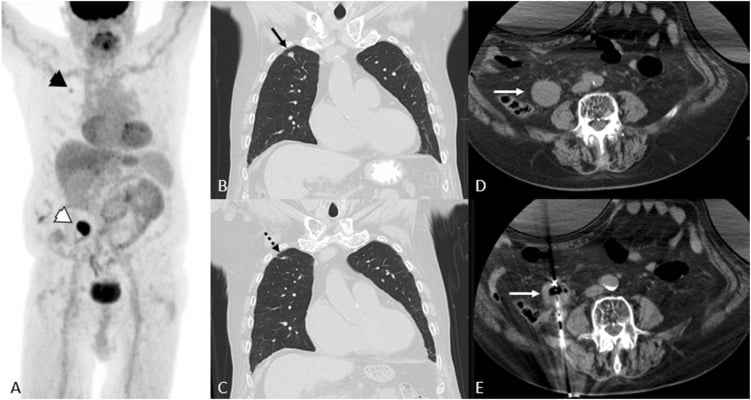

Imaging response assessment for oncology: An algorithmic approach

June 07, 2022. Author(s): Kathleen Ruchalski, Rohit Dewan, Victor Sai, Lacey J. McIntosh, Marta Braschi-Amirfarzan. Source: European journal of radiology open